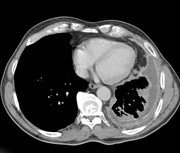

by Dr Sunil Upadhyay – Malignant Pleural Mesothelioma (MPM) is of insidious onset and almost uniformly a fatal disease. Around 90% of the patients can be linked to asbestos exposure. The management outcome of MPM remains dismal. The majority of the patients present with advanced disease, are elderly and have multiple co-morbidities. The common prognostic factors identified are age, sex, performance status, stage and histology. Various treatment modalities used in the management of MPM have included surgery in an extremely small number of patients with or without chemotherapy and/or radiotherapy. Intra-pleural chemotherapy followed by surgery and neo-adjuvant chemotherapy has also been tried but failed. Other novel multi-modality treatments being looked at are intra-pleural photodynamic therapy (PDT) and intra-pleural hyperthermic chemo-perfusion plus surgery. Mature data are appearing from multiple trials.

The role and extent of surgical procedures is terribly controversial. As far as surgery for MPM is concerned, it remains to be standardised. It is often difficult to quantify the location and extent of the disease using current available investigational procedures. We need to question what is the ideal surgery and is maximal cyto-reduction optimal in the surgical management of MPM.

As far as the pleurectomy and de-cortication is concerned, actually it is a marginal resection instead of a maximal resection. Extended pleurectomy/decortication which includes diaphragm and/or pericardium resection is rarely performed. These procedures are preferred for patients with early stage disease or poor pulmonary reserve so that their lung can be spared and morbidity minimised. On the other hand when a thick layer of pleura surrounds the pleural space, the more extensive extra pleural pneumonectomy (EPP) involving an en bloc resection of the lung, visceral and parietal pleura, pericardium and hemi-diaphragm has to be the preferred choice but by an experienced cardiothoracic surgeon. The surgical procedure of choice depends on meticulous patient selection, co-morbidities, extent of the disease and adjuvant therapies following surgery. The surgical outcome is highly dependent on the expertise of the surgeon. It is no good to do pleurectomy or EPP without adjuvant therapy in 2011. Adjuvant chemotherapy has dramatically improved the median overall survival to 30 months in most of the studies by stage and operation. For early stage cases, with the use of postoperative adjuvant treatment median survival of up to 44 months has been reported.1,2 Moreover, whether adjuvant therapy had been delivered or not, pleurectomy was at least equivalent to EPP in both early and late stage.